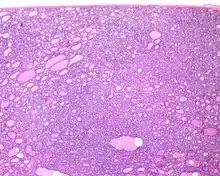

Histologic features

Several specific features must be identified for the tumor to be classified in this new category, while exclusion criteria should also be evaluated.

1) Encapsulated or partially encapsulated. The tumors are usually very well delimited or circumscribed, with the majority encapsulated, surrounded by a well formed fibrous connective tissue capsule.

2) Complete absence of invasion of any kind in a tumor that has been thoroughly and carefully evaluated with the whole capsule of the lesion sampled.

3) Predominantly follicular pattern of growth. Papillary structures should not be present. Further, solid, insular, or trabecular architecture must be <30% of the overall tumor for this category to still apply. Colloid (the material that thyroid follicular cells create) is easily identified throughout.

- ↑ Image by Mikael Häggström, MD. Reference for findings: Rachel Jug, M.B.B.Ch., B.A.O., David Poller, M.D., Xiaoyin "Sara" Jiang, M.D. "NIFTP". Pathology Outlines.